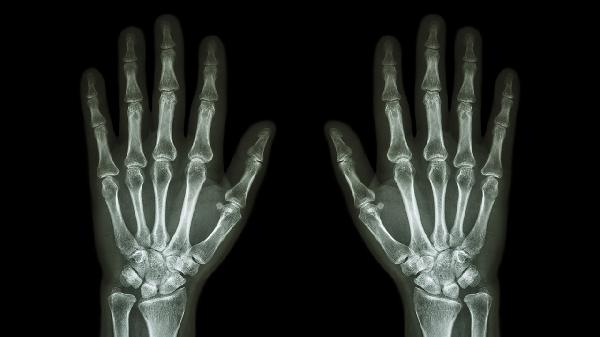

关节软骨磨损导致骨面直接摩擦可能产生粗糙弹响,多见于中老年人群。可能与关节退变、机械负荷过重有关,常伴随晨僵和活动后疼痛。可遵医嘱使用硫酸氨基葡萄糖胶囊、双醋瑞因胶囊等软骨保护剂,或局部注射玻璃酸钠注射液。

滑膜炎症导致关节结构破坏可能引发病理性弹响,属于自身免疫性疾病。可能与遗传和环境因素共同作用有关,典型表现为对称性关节肿痛。需规范使用甲氨蝶呤片、来氟米特片等抗风湿药,配合生物制剂如阿达木单抗注射液控制病情。

日常应注意避免手指过度负重或长时间保持固定姿势,寒冷季节注意手部保暖。若弹响伴随红肿热痛、关节变形或功能受限,建议尽早就诊风湿免疫科或骨科,通过血液检查、X线或核磁共振明确病因。规律进行手指伸展运动有助于维持关节灵活性,饮食可适当增加富含欧米伽3脂肪酸的深海鱼类。